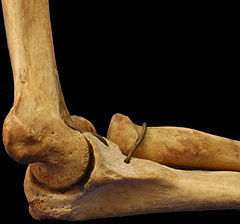

Troclear: Es uniaxial, movimientos en un solo plano (Sagital), forma de bisagra. Ejemplo: Humerocubital.